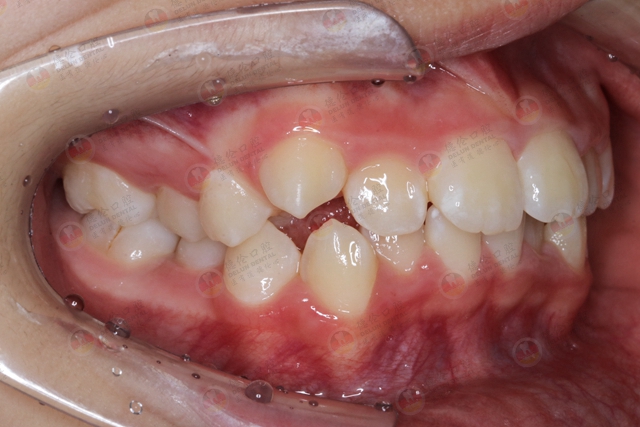

因此,这些挤在一起的牙齿就很容易出现牙列拥挤、龅牙或者是地包天等畸形症状。因此,拔牙就是拔掉将影响矫正效果的多余牙齿。

牙列拥挤的情况下,不拔牙强行做矫正会让牙齿看起来“散出去”。原本正常的侧脸反而被破坏,嘴巴部分看上去突出去,说话或者笑的时候会有“满嘴都是牙齿”的感觉。

大多数小伙伴的牙齿不齐,会出现在“虎牙”等尖牙位置。因为虎牙的萌出时间比较晚,所以在牙齿拥挤的情况下会没有位置给尖牙正常生长空间。

然而,“虎牙”在嘴巴、面容美观方面起到了关键作用。其中一个重要作用就是支撑面部的饱满度,在你微笑的时候会露出6颗前牙,形成一道弧线。而非一条死板的直线。如果虎牙过度前突,可以通过矫正治疗,让尖牙重新摆正。